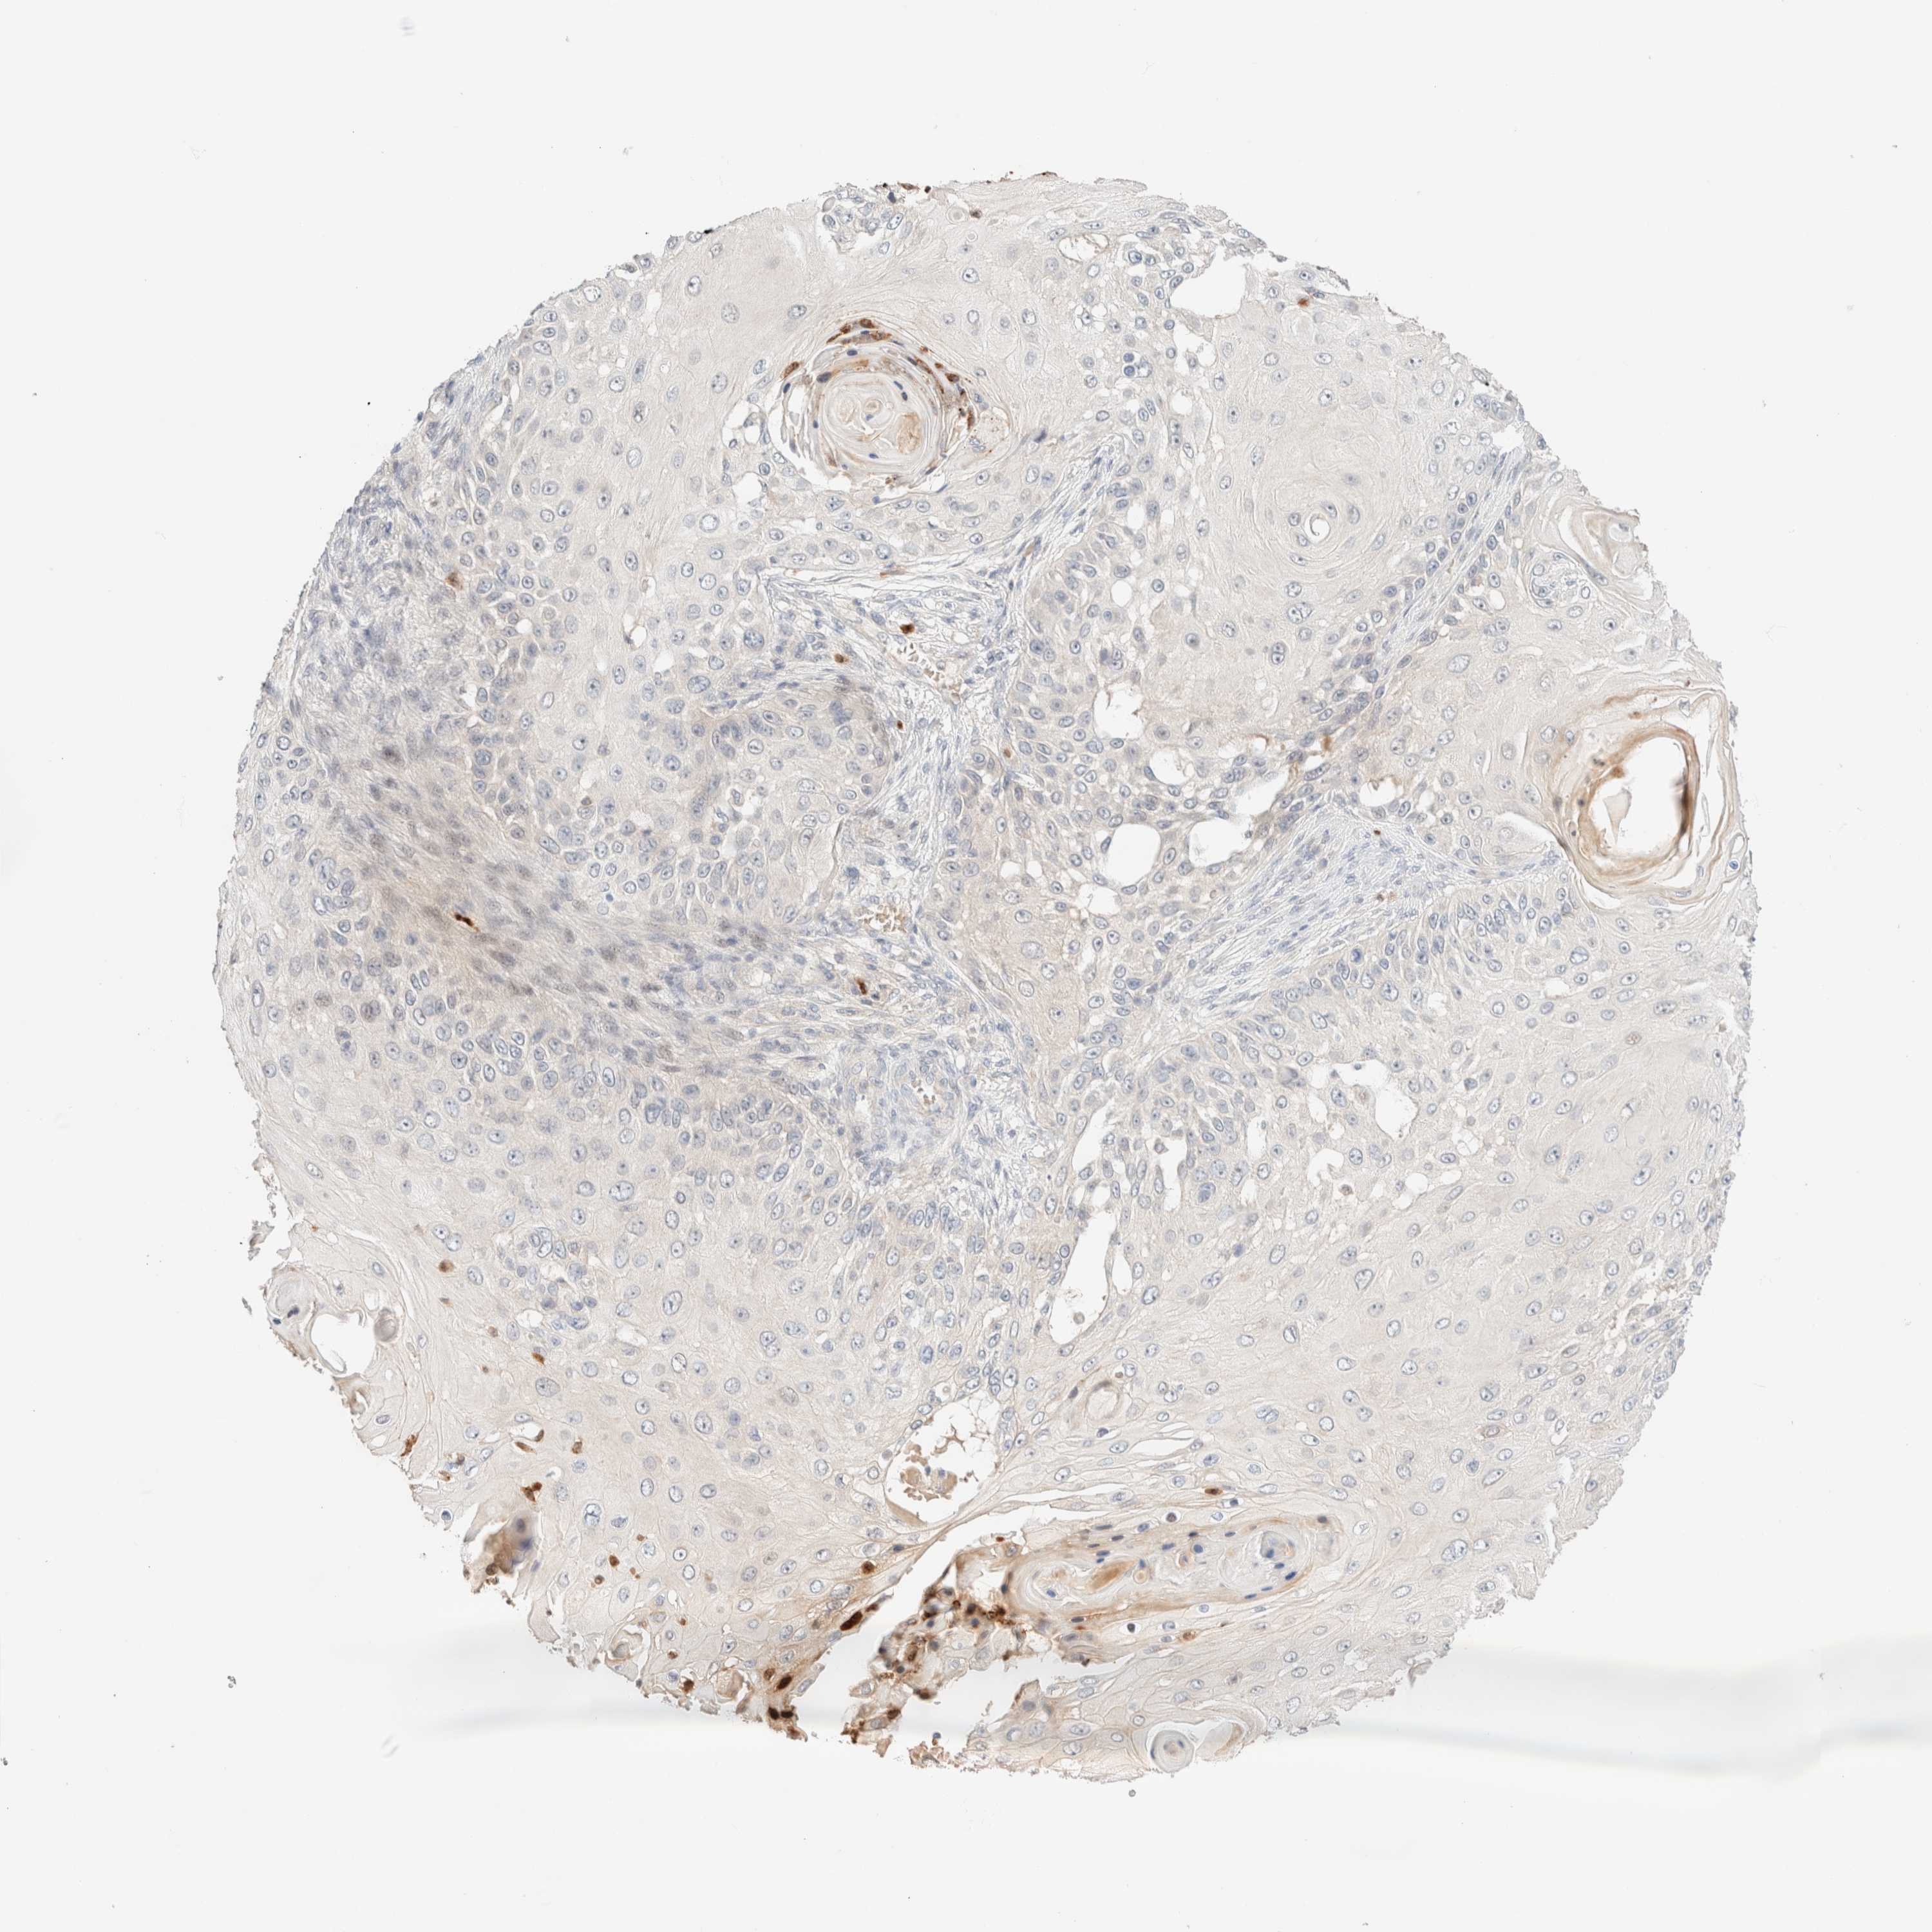

SKIN CANCER - Protein expressioni

A mouse-over function shows sample information and annotation data. Click on an image to view it in a full screen mode. Samples can be filtered based on level of antibody staining by selecting one or several of the following categories: high, medium, low and not detected. The assay and annotation is described here.

Each image is clickable and will lead to virtual microscopy that enables deeper exploration of all samples and also displays staining intensity scores, fraction scores and subcellular localization as well as patient and tissue information for each sample.

Antibody HPA024553

Staining

Low

Intensity

Weak

Quantity

<25%

Location

None

Squamous cell carcinoma, NOS